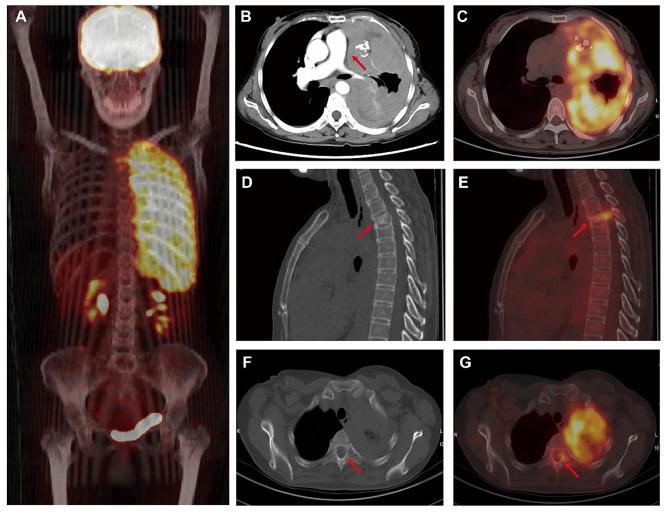

A 51-year-old woman was admitted to our hospital with dyspnea and chest pain. Upon imaging examination, she was found to have diffuse and nodular pleural thickening on the left side, collapse of the left lung and a compression in the second thoracic vertebrae. All lesions showed significant F-FDG uptake on F-FDG PET/CT examination. Furthermore, she exhibited T-cell lymphocytosis in her peripheral blood, lymph nodes, and bone marrow. After ruling out malignant pleural mesothelioma (MPM), lung cancer with pleural metastasis, and T-cell lymphoma, the definitive diagnosis asserted was ectopic pleural thymoma with T-cell lymphocytosis and bone metastasis.

一名 51 岁女性因呼吸困难和胸痛就诊于我院。影像学检查发现左侧弥漫性和结节性胸膜增厚,左肺塌陷,第二胸椎受压。所有病变在 F-FDG PET/CT 检查中均显示明显的 F-FDG 摄取。此外,她的外周血、淋巴结和骨髓均出现 T 细胞淋巴细胞增多。在排除恶性胸膜间皮瘤(MPM)、肺癌伴胸膜转移和 T 细胞淋巴瘤后,明确诊断为胸壁胸腺肿瘤伴 T 细胞淋巴细胞增多和骨转移。